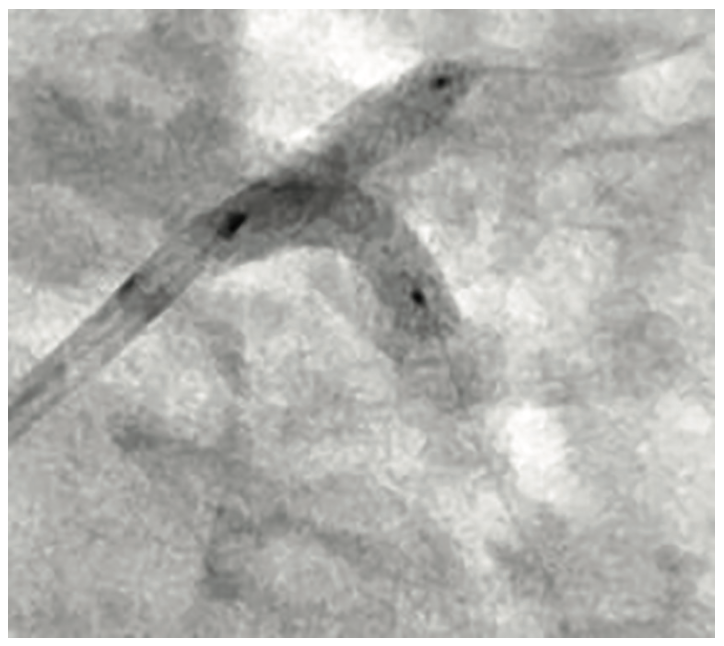

Right radial access was obtained with a radial 7 French (Fr), 10 cm length GLIDESHEATH SLENDER® Introducer Sheath (Terumo Interventional Systems) and the ostium of the LMCA was engaged with a 7 Fr Extra Backup (EBU) 3.5 guide catheter (Medtronic) to facilitate bifurcation stenting. The initial angiogram images revealed a worsening of the distal LMCA stenosis, now at 80% and extending into the ostial LAD (Figure 1). A Runthrough NS Izanai White guidewire was advanced across the lesion into the distal LAD and a Runthrough NS Izanai Blue was advanced across the lesion into the distal LCx with minimal difficulty. To facilitate intravascular ultrasound catheter delivery, the distal LMCA/ostial LCx was predilated with a semicompliant 2.0 mm x 15 mm Takeru PTCA Balloon Dilatation Catheter at nominal pressure (8 atmospheres). IVUS of the LCx was performed first, followed by IVUS of the LAD, and showed severe, concentric calcification of the distal LMCA and ostial LAD/LCx (Figure 2). For plaque modification and lesion optimization prior to stent deployment, a 3.5 mm x 12 mm C2+ intravascular lithotripsy balloon (IVL, Shockwave Medical) was advanced first into the LCx and subsequently into the LAD. The LMCA to proximal LCx and the ostial LAD were treated with 120 pulses with 12 inflations of the IVL balloon. Angiography revealed no evidence of dissection following IVL; however, there was some recoil in the ostial LCx, for which cutting balloon angioplasty was performed with a 3.5 mm x 15 mm Wolverine balloon (Boston Scientific) in the ostial LCx and extending back into the distal left main. Next, the decision was made to proceed with bifurcation stenting using a culotte strategy. A 3.5 mm x 20 mm Synergy Megatron drug-eluting stent (DES, Boston Scientific) was placed from the distal LMCA into the proximal LCx (Figure 3). Following post dilation of the DES with a 3.5 mm x 15 mm noncompliant balloon, a new Runthrough NS Izanai White was used to re-wire the LAD through a side strut of the LMCA-LCx DES. A semicompliant 3.0 mm x 12 mm Takeru PTCA Balloon Dilatation Catheter crossed into the LAD with minimal difficulty and was used to dilate the stent struts to facilitate delivery of the LMCA-LAD DES. A noncompliant 3.0 mm x 15 mm balloon inflation was performed to optimize the LAD lesion further. A 3.5 mm x 16 mm Synergy Megatron DES was then placed in the proximal LAD, overlapping with the prior stent in the LMCA (Figure 4). Following post dilation of the LMCA-LAD DES with a 3.5 mm x 15 mm noncompliant balloon, the proximal portion was optimized (proximal optimization technique [POT]) with a 4.0 mm x 8 mm noncompliant balloon. The LCx was then rewired with the Runthrough NS Izanai White through a side strut of the LMCA-LAD stent and the Runthrough NS Izanai Blue was placed in the LAD. Following serial dilations of the LMCA-LAD stent struts with Takeru PTCA Balloon Dilatation Catheters, kissing balloon inflation of both the LAD and LCx extending back into the LMCA was performed with a 3.5 mm x 15 mm noncompliant balloon in the LCx and a 3.0 mm x 15 mm noncompliant balloon in the LAD (Figure 5). Repeat IVUS of both stents back into the LMCA was performed, demonstrating adequately expanded and apposed stents with no evidence of edge dissection. Final POT was performed in the LMCA with a 4.5 mm x 8 mm noncompliant balloon. Final angiography revealed TIMI-III flow, no evidence of proximal or distal edge dissections, no perforation, and <5% residual stenosis (Figure 6). The total contrast volume was 55 mL with a case length of 1.5 hours. The patient was discharged three days later without complication.